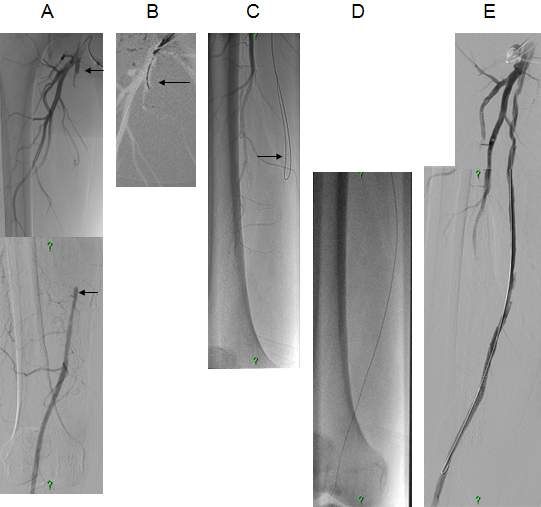

Due to technical reasons (antegrade or retrograde puncture, contralateral or ipsilateral puncture, femoral or brachial puncture), prognosis and risks, three types of levels are distinguished: iliac (Figure 4), femoro-popliteal (Figure 5) and crural (infragenual) (Figure 6) endovascular therapy. The latter two composes the infrainguinal group. PTA and stent placement are usually technically easier (with the exception of long occlusions), have a longer patency and carry lower risk in the iliac group compared to the other two groups. Patency following crural PTA is the worse and carries the highest risk, therefore, it is usually indicated only in Fontaine stages III and IV. The number of amputation per capita in Hungary is larger than that in most other European countries. In patients with gangrene and diabetes mellitus, crural PTA may save a large number of amputations. In case of successful PTA, limb salvage rate is considerably higher than crural patency rate, since perfusion needed for a healing ulcer or gangrene is considerably higher than for the basic functions (collateral arteries may be sufficient for such purpose). Subintimal PTA is performed more and more frequently: when luminal recanalisation is technically not possible, intentional dissection is done using the hydrophilic guidewire along the occluded segment; then, distally to the occlusion, the guidewire is directed back to the normal lumen and a new channel is formed along the normal lumen–dissected channel–normal lumen route (Figure 5).

Figure 5. Subintimal percutaneous transluminal angioplasty (PTA). Panel A: Superficial femoral artery has been occluded from its origin with a stump (upper arrow). Refilling occurs at the distal SFA (lower arrow), total length of the occlusion is approximately 18 cm. Panel B: The white background („roadmap”) shows the profunda femoral artery. The guidewire (in black on the white background; arrow) is at the beginning of the occluded segment. Panel C: the guidewire forms a loop (arrow), and gradually proceeds into the subintimal space. Panel D: the tip of the guidewire reached the normal popliteal artery lumen, there is no loop formation any longer. Panel E: Following balloon dilation of the whole segment, SFA shows quick flow in its entire length.